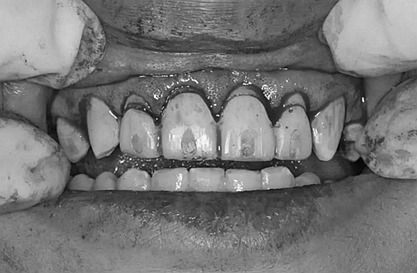

因為對我們的治療需要分多次進行,因此初次治療后做了臨時牙

第二次治療是半個月后,這次做了根管充填后將覆蓋在我們身體上的一部分牙齦切除,讓我們埋于牙齦下的身體暴露了一部分,也就是醫(yī)生說的冠延長術。這是為了讓我們變得美觀一些。

根管治療

冠延長術

兩周后,主人帶我們往醫(yī)院拆線,取模,比色,為我們重新量身定制了一套堅固的“外套”。

第5次復診的時候,終于讓我們4個兄弟恢復了正常的容顏。